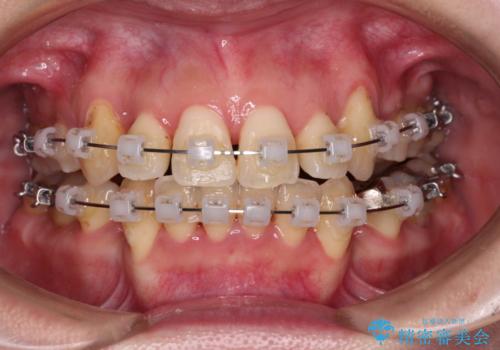

【モニター】上下の八重歯を治したい ワイヤー装置による矯正治療

- クリアブラケット

- 上下前歯のデコボコを気にして来院された患者様です。

デコボコが強いため、非抜歯で矯正をすると出っ歯仕上がりとなるため、上下左右の第一小臼歯4本を抜歯することとしました。